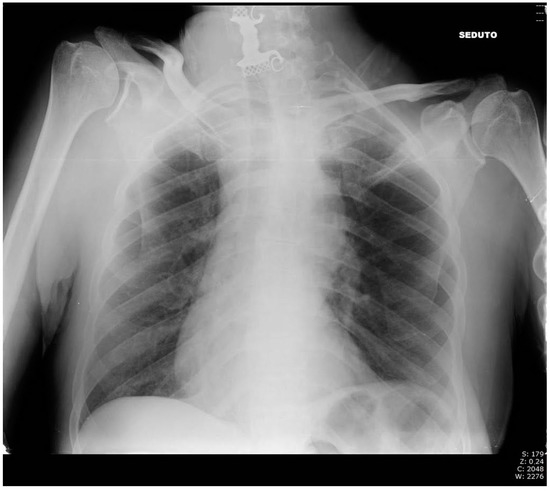

2. Case Presentation